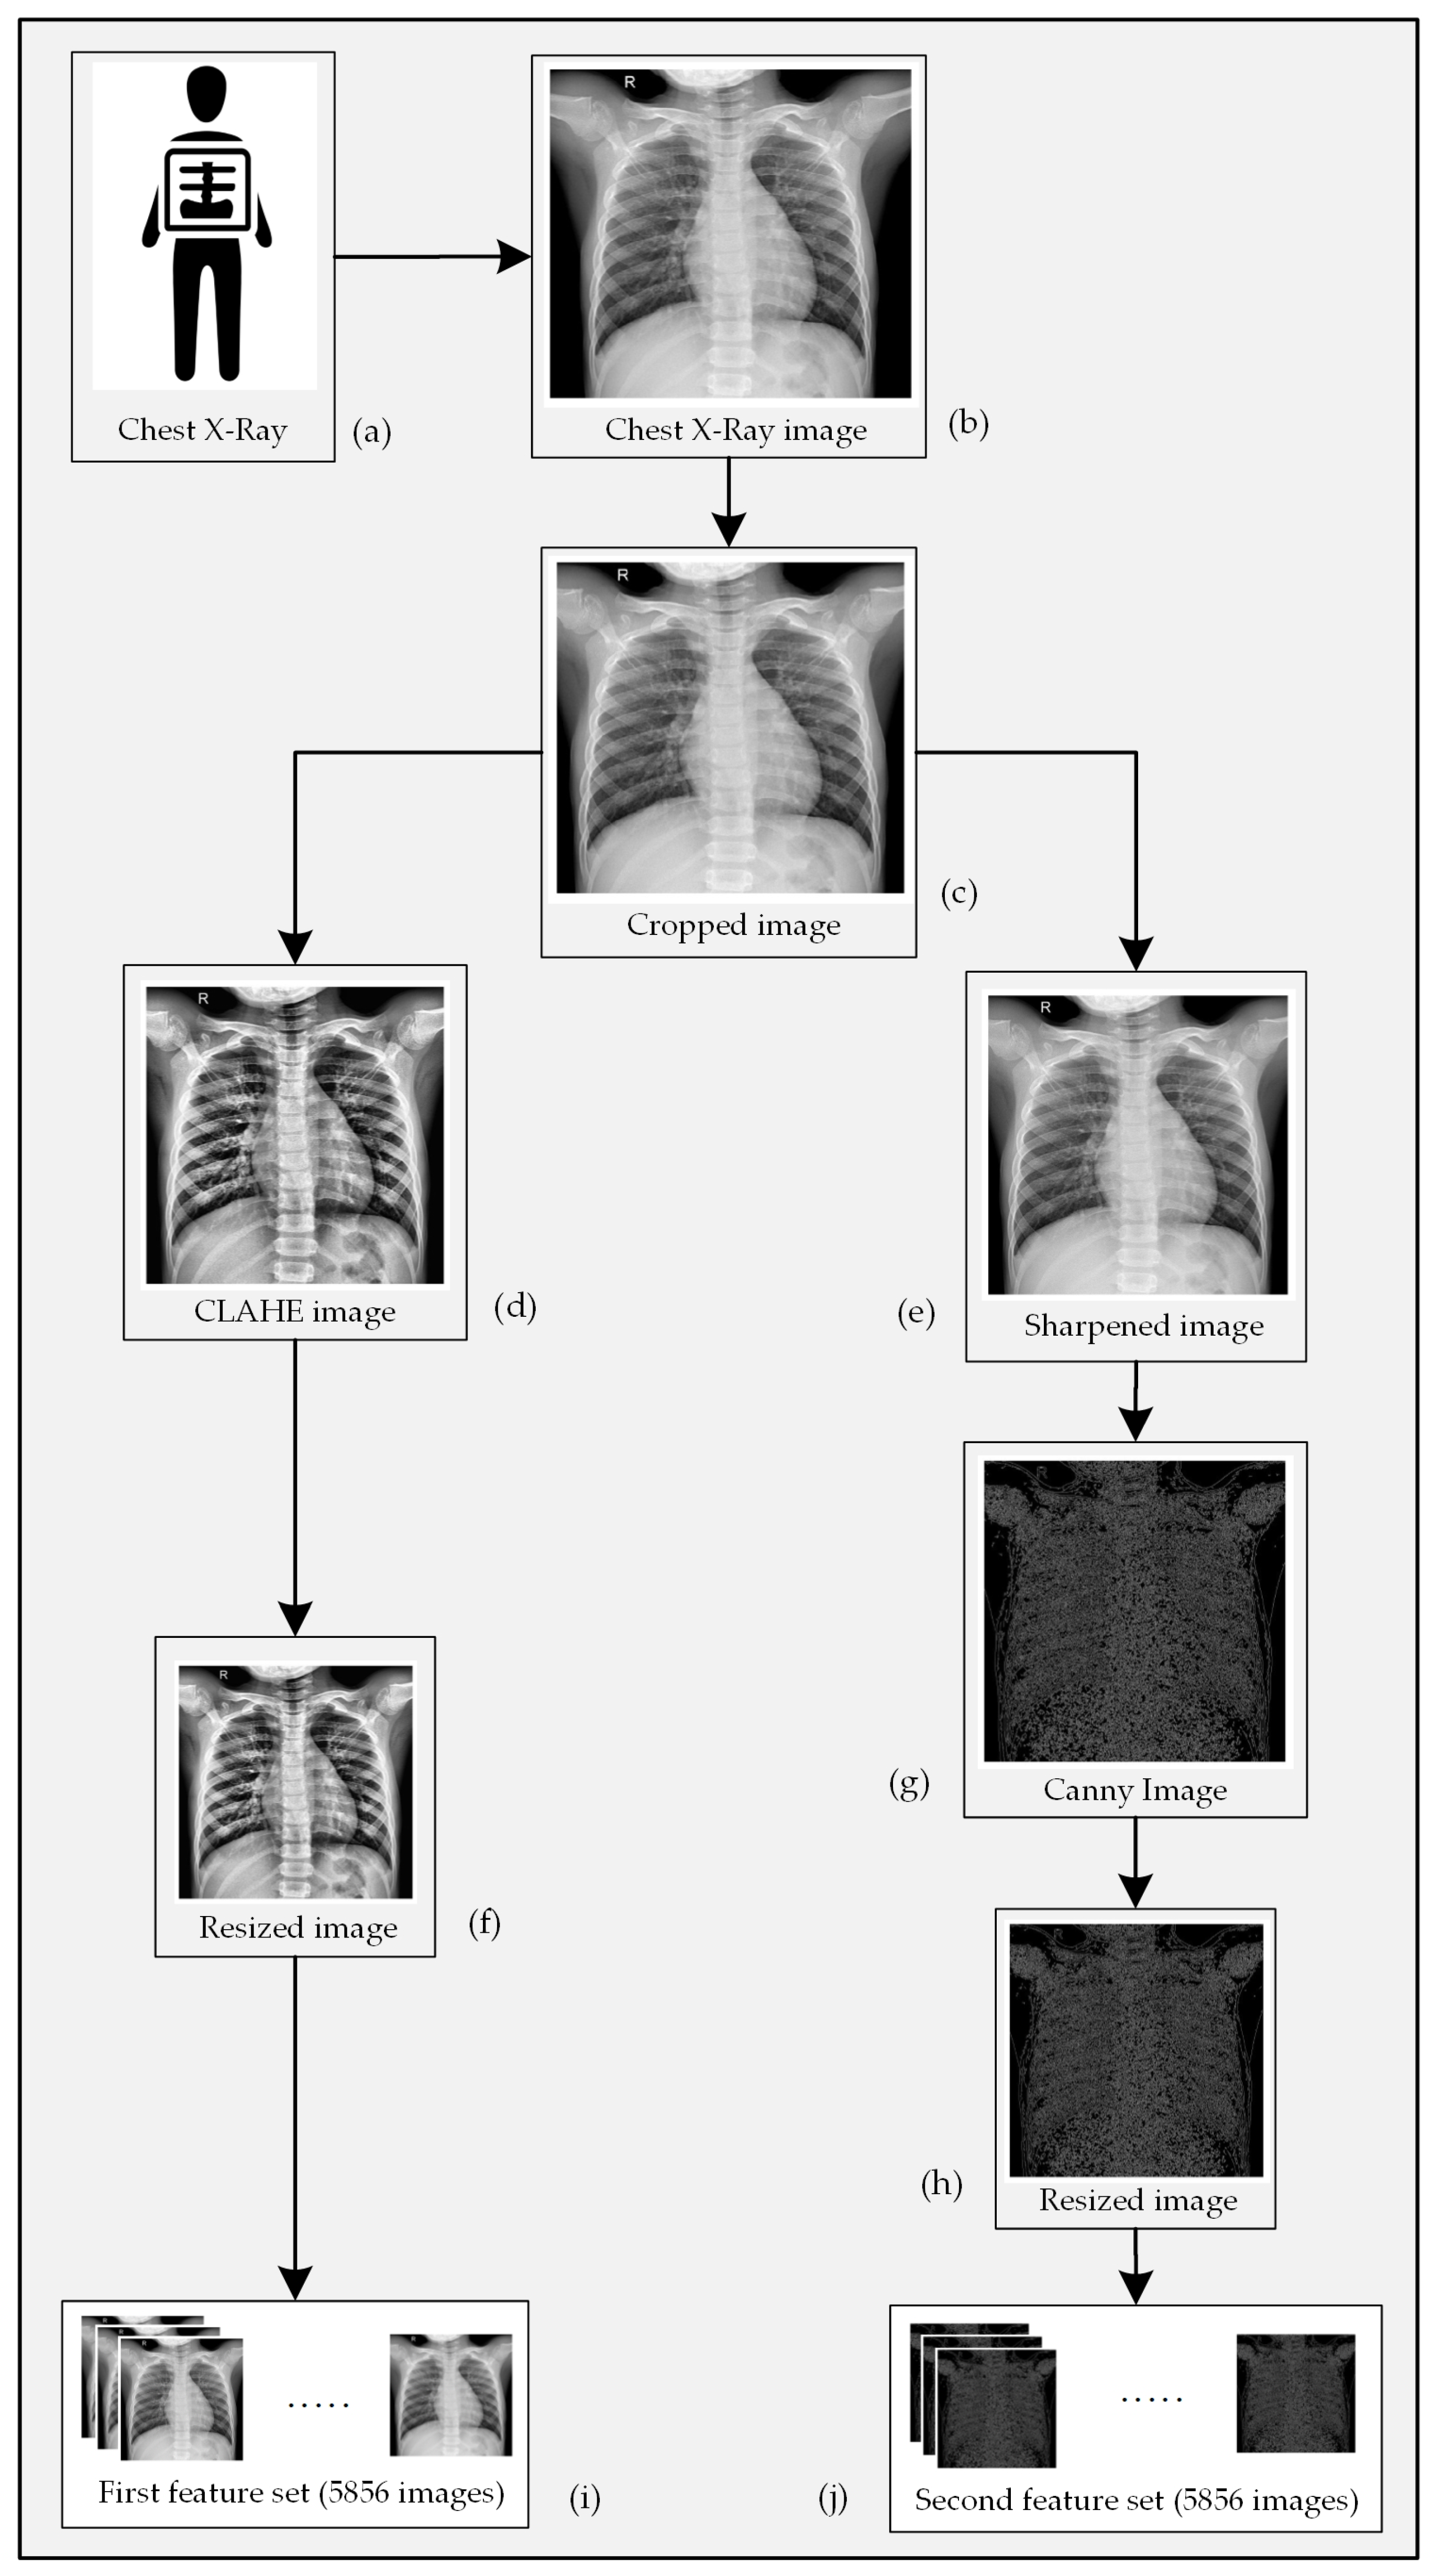

2. Methodology

2.2. Image Cropping

2.3. Image Preprocessing

2.3.1. Data Preparation for the 1st Channel

2.3.2. Data Preparation for the 2nd Channel